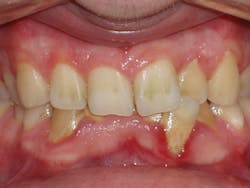

Four weeks later, Evin began his clear aligner treatment (see Figure 1). He was seen for follow-up clear aligner visits at six-week intervals until his treatment was completed. During his clear aligner treatment, Evin maintained three-month recalls with the hygienist. His home care was excellent, in part due to the benefit of aligners being removable.

Figure 1

The six-week follow-up visits with Evin were eye-opening! I had the opportunity to observe his periodontal condition improve at each interval. After 30 aligners, or 15 short months, Evin's clear aligner orthodontic treatment was completed and final photos were taken. His bite was checked to confirm we had achieved our initial goal. Evin now had the appropriate overbite, overjet, and class I occlusion with proper posterior intercuspation with no interferences.

Evin is a perfect example of this. He always had beautiful teeth. Dr. Miraglia could see that they were just in the wrong place! Insufficient space, as a result of improper arch forms is the cause of crowding, not "crooked" teeth (see Figure 1).